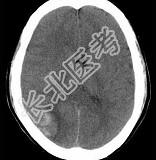

- 单项选择题男,37岁, 头痛、头晕1年余,加重3天, CT检查如图所示,最可能的诊断是 ( )

A、脑血管畸形并出血

B、转移瘤并出血

C、颅内动脉瘤

D、脑出血

E、脑膜瘤并出血